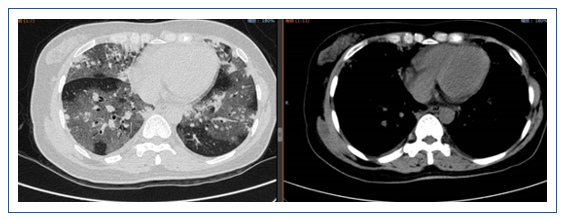

此例患者为起病急骤,病程较短,无基础疾病,胸部CT显示弥漫性磨玻璃影,结合其临床表现和实验室检查结果,主要考虑是否与病毒感染相关。另外,患者痰中带血丝,但病毒学检查为阴性,建议尽早行支气管肺泡灌洗。在治疗方面应以抗病毒为主,如果患者呼吸困难比较严重,可以适当加用一些激素。

该患者急性起病,发热,痰中带血,病情较重,但影像学改变并不典型。患者胸部CT示双肺磨玻璃影,双下肺可以见与支气管伴行的肺血管明显增粗,右下肺可见血管影扩张,中叶胸膜下片状高密度影,左下肺血管影扩张较明显。目前在诊断方面考虑感染性病变和非感染性病变。非感染性病变主要考虑两类,一类是非肿瘤相关疾病,如自身免疫性疾病,另一类是肿瘤相关病变,如淋巴瘤、血液系统疾病等。结合患者的临床表现和检查结果,我个人认为非感染性疾病的可能性较大,仍需进一步检查明确,如支气管肺泡灌洗、肺活检等。